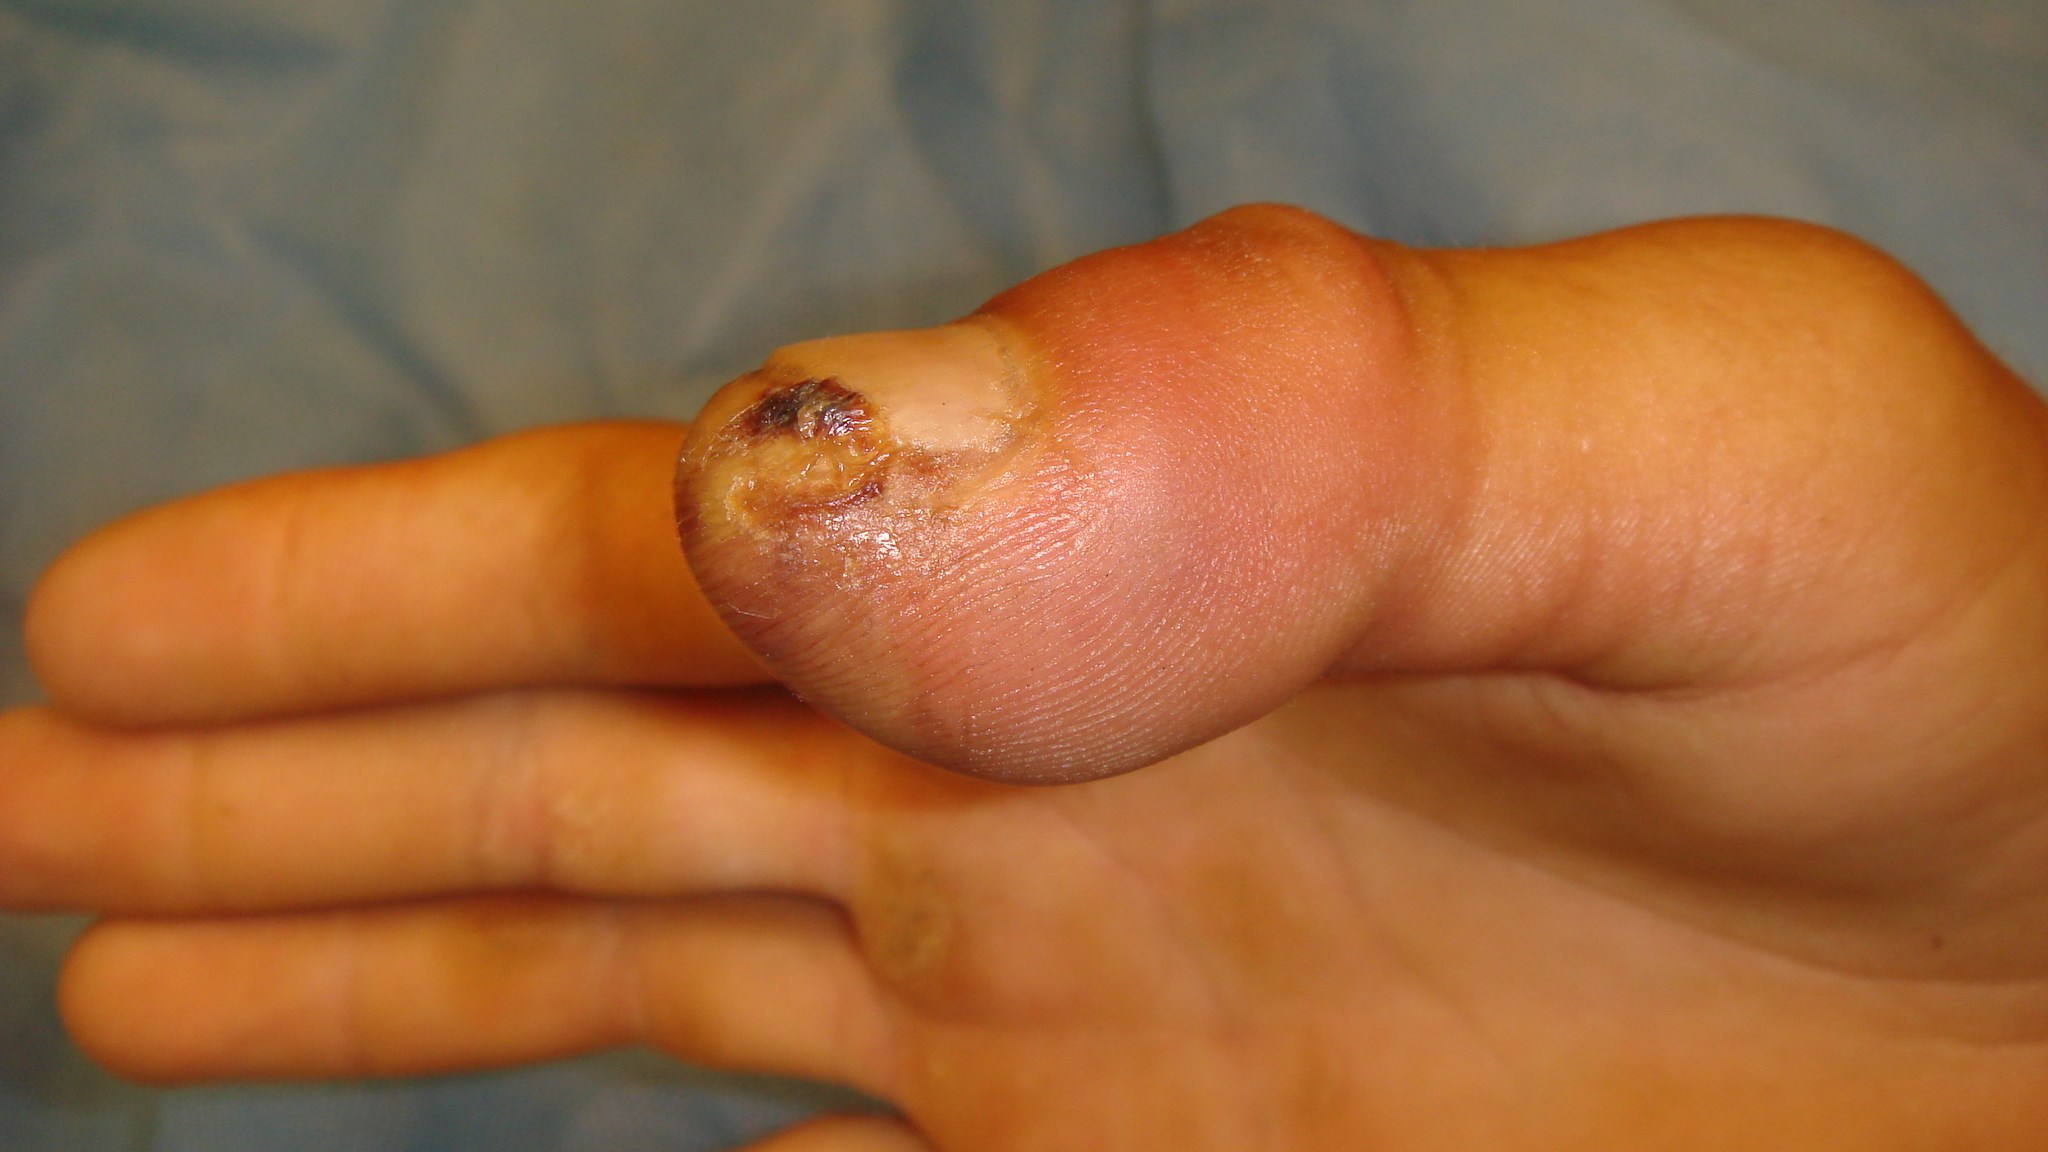

Fingertoppsskada utan blottlagt ben

Fingertoppsskador utan blottlagt ben behandlas vanligen bäst med konservativ regim. Det vill säga initial rentvättning av såret och därefter omläggningar med förband som inte helt torkar ut sårytan. Läkningen bygger på att epitelet växer in från sidorna av sårkanten varför det kan ta flera veckor eller månader innan toppen är fullt läkt.

Att det är mödan värt att vänta beror på att man slipper korta fingret eller tummen ytterligare för att få primär sårläkning. Hudtransplantat är ett annat alternativ men jämfört med det blir både form och kvalitet på toppen betydligt bättre efter sekundärläkning.